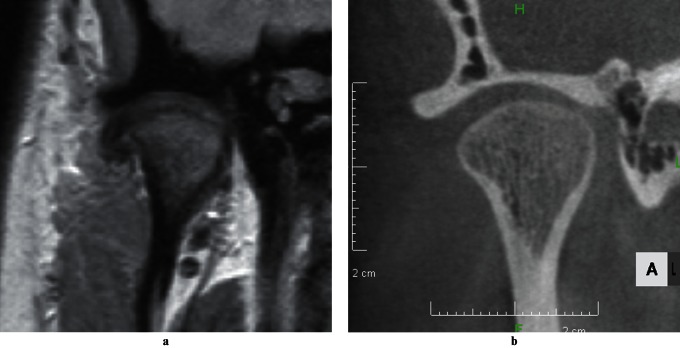

Figure 2.

MRI (a) and CT (b) images of total disc displacement with reduction

The study included 60 joints with MRI-confirmed DD in 57 subjects aged 12–20 years (mean age 14.8 years) from a pool of post-orthodontic patients for retrospective analysis of their disc positions on LCBCT images. The MR and LCBCT images used in the study had been obtained as part of the initial examination upon informed consent, as patient history and chairside examination22 had indicated the need for objective TMJ status assessment by diagnostic imaging prior to orthodontic treatment. Subjects meeting the following inclusion criteria were enrolled based on the temporal order of the initial visit between January 2006 and September 2009: (1) no history of trauma to the face; (2) no DJD; (3) no excessive joint effusion;23 (4) no major CO–CR discrepancy at the joint level; (5) no hypertrophy of the disc; and (6) no thinning of the disc. The absence of DJD was confirmed on open-mouth MR images according to the severity and non-reducing status of DD, and joints with marked osseous alterations on CBCT images were excluded.24 T2 weighted MR images were used to detect excessive joint effusion. CO–CR discrepancies at the joint level were checked with a condylar position indicator (CPI; Panadent, Grand Terrace, CA) to exclude vertical and anteroposterior discrepancies of 1.8 mm or more and transverse discrepancies of 0.6 mm or more.25 Overt hypertrophy or thinning of the disc was identified with MRI. The subjects who met these criteria were divided into four DD groups: partial DD (PDD), total DD with reduction (TDDWR), lateral DD (LDD) and medial DD (MDD). PDD was defined as a posterior band of the disc displaced to the middle third of the eminence on one or two of the three sagittal (medial, central and lateral) MR slices examined (Figure 1a). TDDWR was defined as a more advanced stage of DD where one or two of the three sagittal slices revealed the displacement of a posterior band down to the inferior one-third of the eminence, the remaining sagittal slice(s) not showing a posterior band within the superior one-third of the eminence (Figure 2a). Figure 3 is a schematic representation of normal disc position, PDD and TDDWR in the sagittal plane. A medial or lateral component of DD had to be less than one-quarter of the disc width in the coronal plane for both PDD and TDDWR. LDD was defined as one-third to one-half of the disc displaced laterally on the coronal MR slice, but the posterior band was retained within the superior half of the eminence on the lateral sagittal slice (Figures 1 and 4). Figure 5b illustrates LDD, as defined in this study, compared with the normal disc position in the coronal plane (Figure 5a). MDD was defined as one-third to one-half of the disc displaced medially (Figure 5c) on the coronal MR slice.